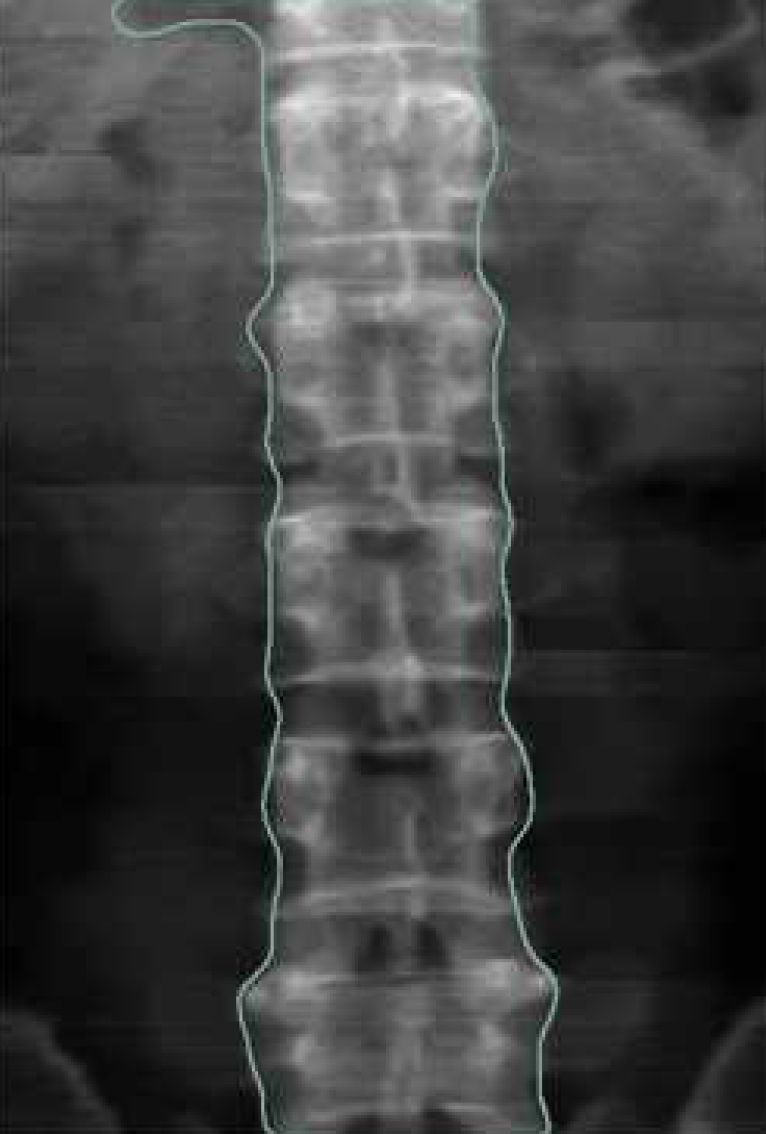

32 Channel Fan Beam

Scan Area 15 Cm x 20 Cm

Scan site Spine, Femur, Forearm

Spine: L1 ,L2, L3, L4, L1-L3,L1-L4,L2-L3,L2-L4,L3-L4

مشخص کردن مناطق نواحی اسکن ROI بصورت اتوماتیک

قابلیت تشخیص فاصله بین مهره در spine

حداکثر مساحت مورد اسکن: طول :20 Cm عرض:15 Cm